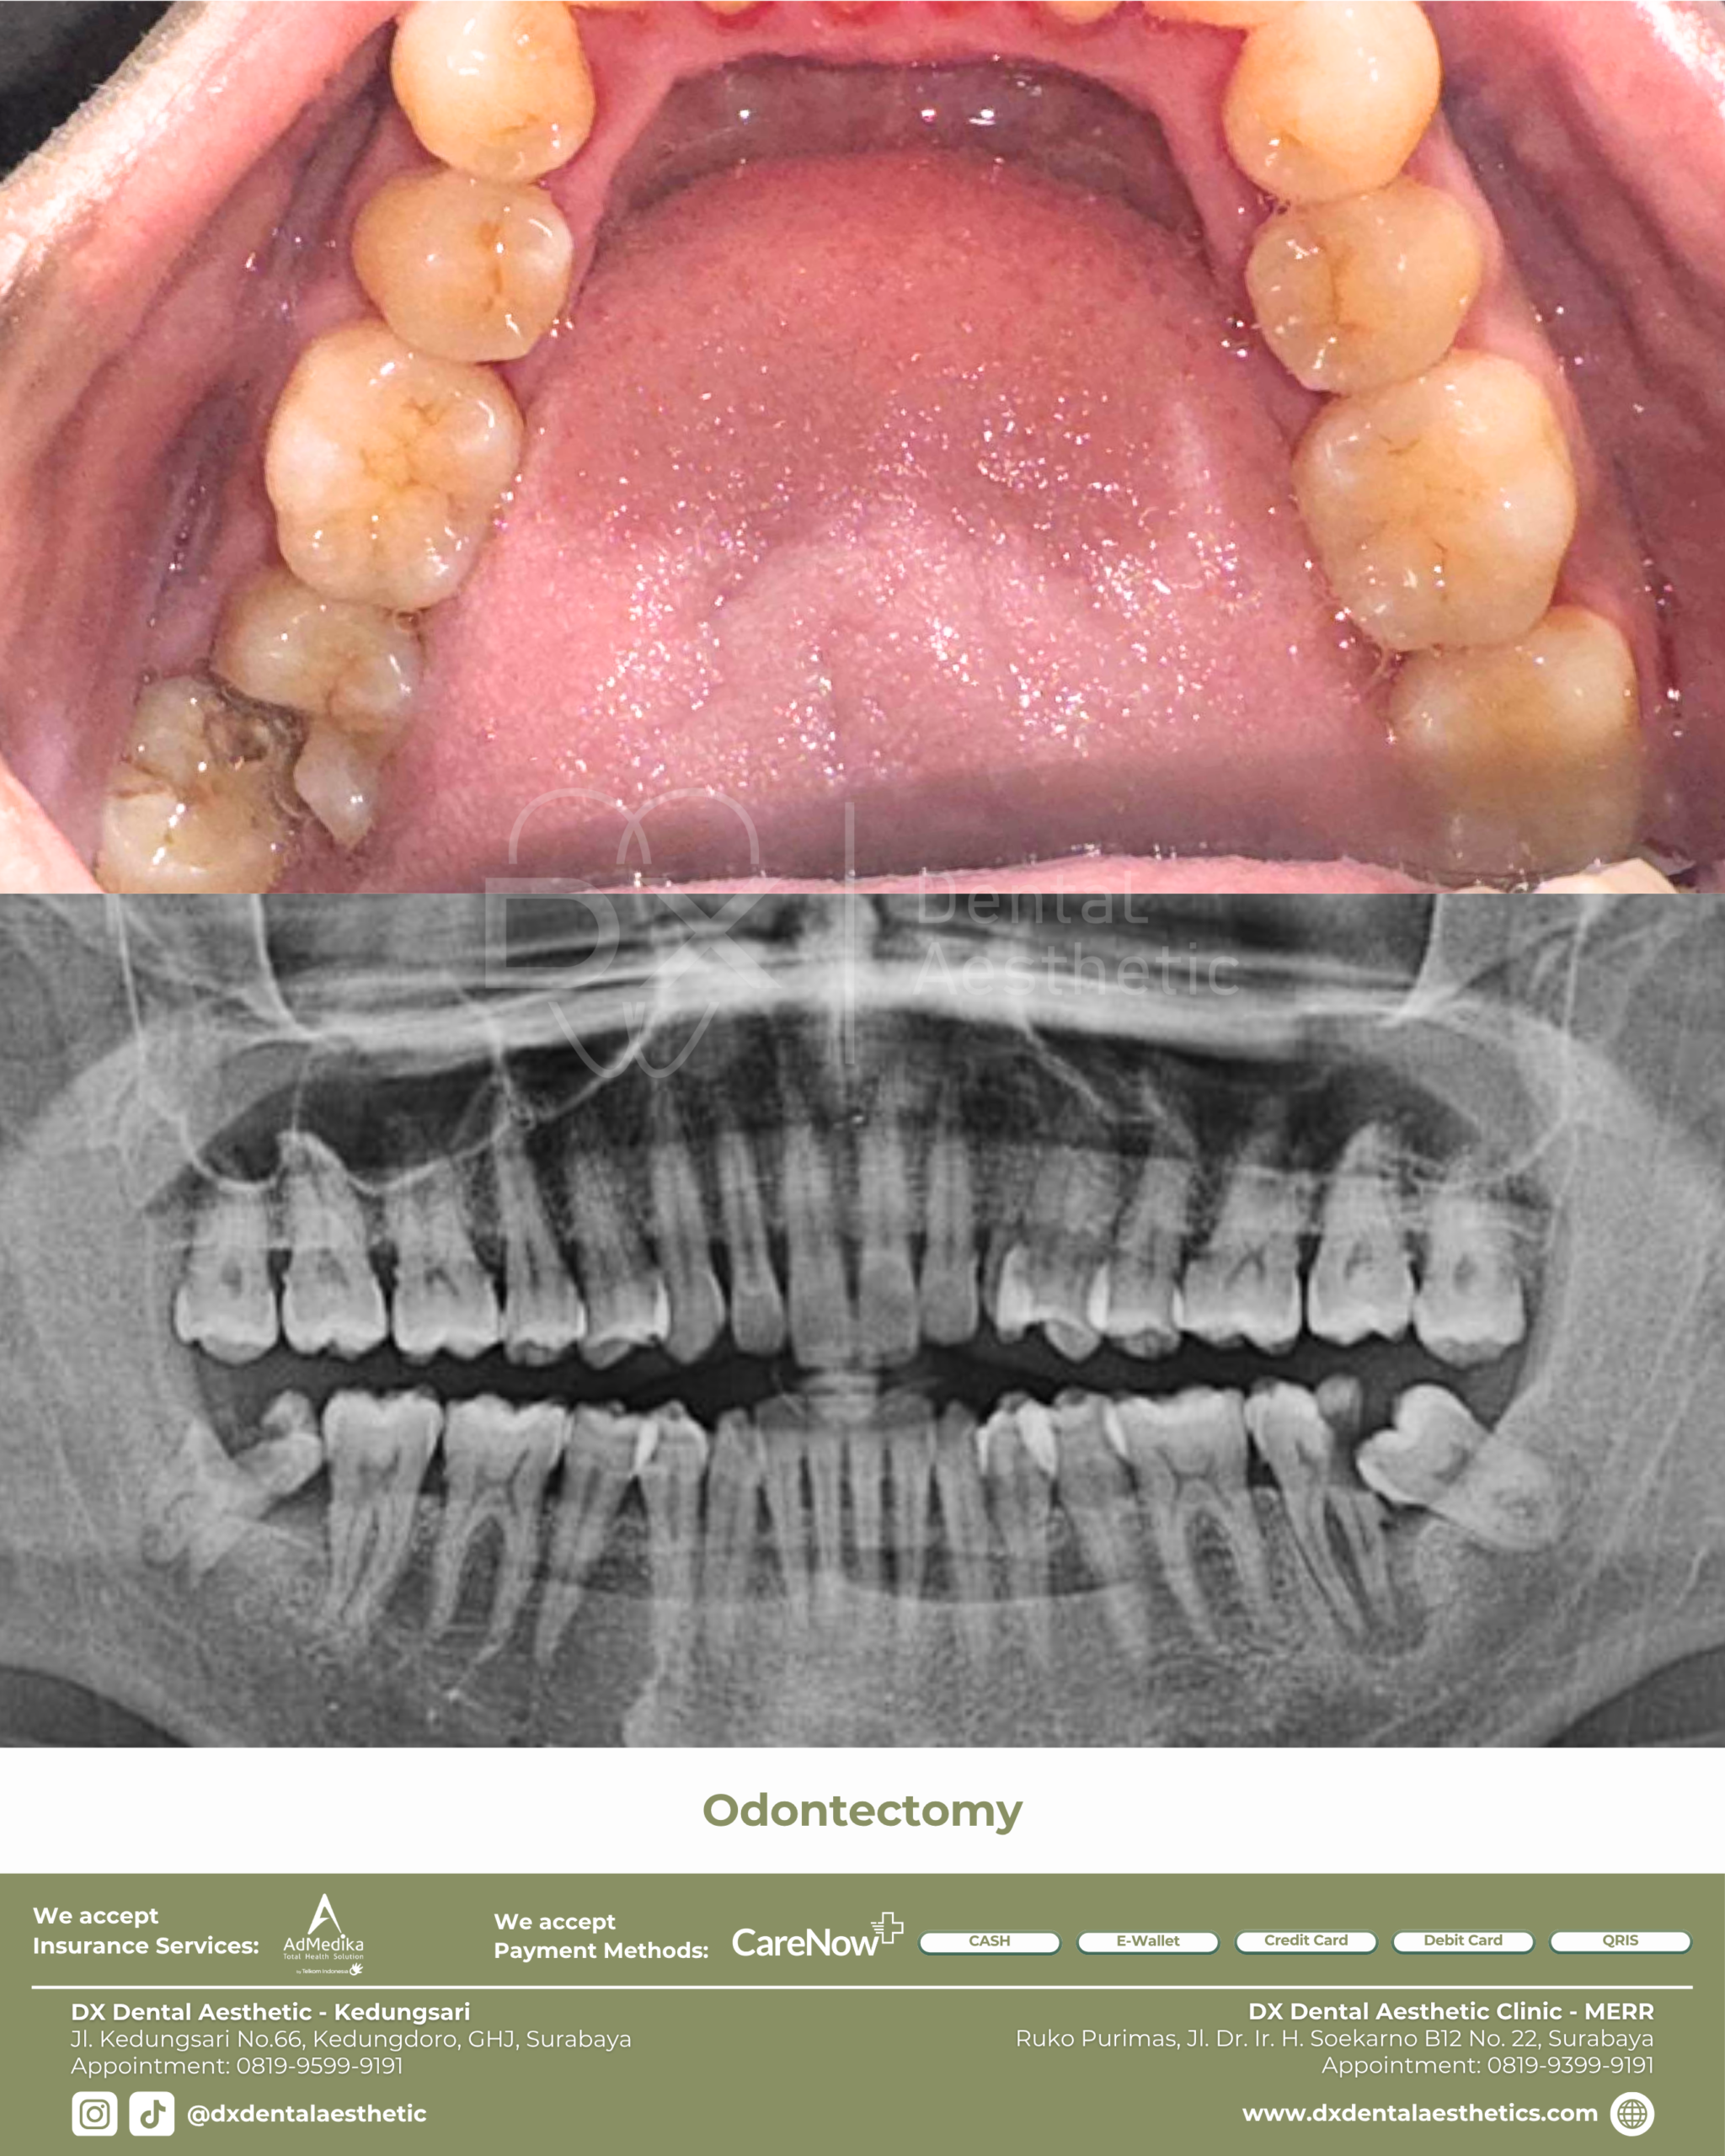

before after

Sebelum dan sesudah treatment di DX Dental Aesthetic